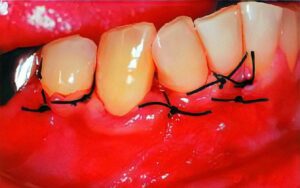

歯周病の進行した方では、歯肉を開いて歯石を除去する歯周外科手術を行うこともあります。